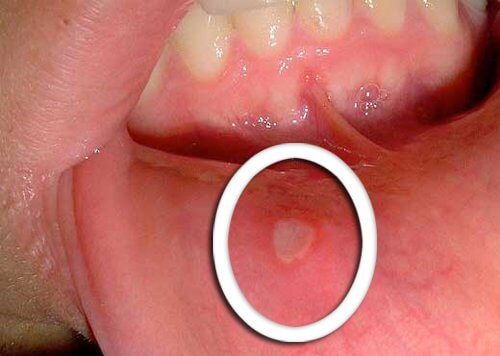

- 口咽癌的最早症狀是不會癒合的小潰瘍。

- 在舌頭、牙齦或嘴唇上出現紅色或白色的傷口是典型症狀。

- 請注意任何沒有在幾天內改善的不尋常變化,並讓你的醫生知曉。